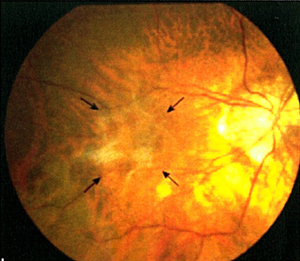

黃斑點視網膜前膜增生(圖2)是本港常見眼疾之一,治療方法包括切除玻璃體及移除前膜。採用內界膜去皮最新治療能讓患者的視力獲得改善,而接受初次手術後復發率屬低。

![]() 圖2:深近視人士患上黃斑點視網膜前膜病變(手術前攝)。 |